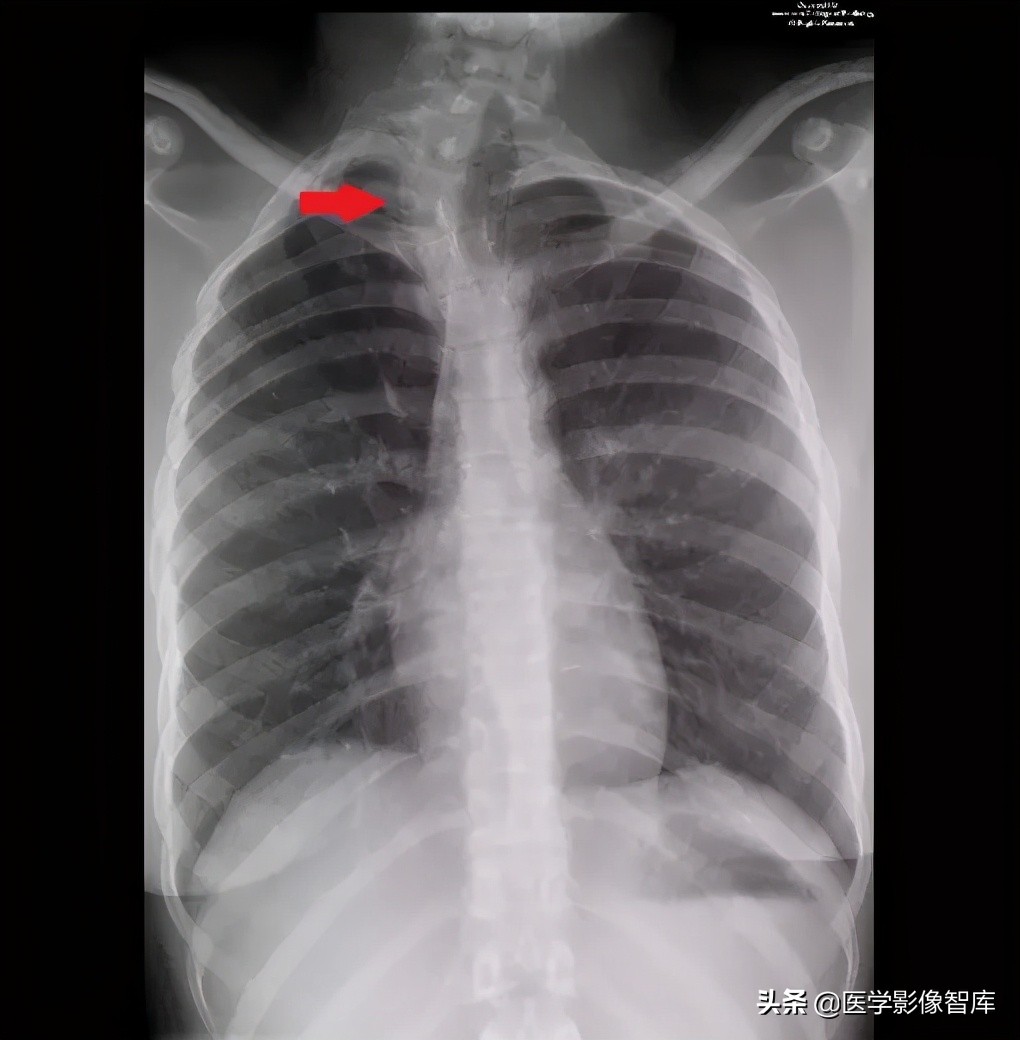

图 10. 胸部 X 线正位片显示椎体发育异常(红色箭头)和编外肋(15 右肋和 14 左肋)